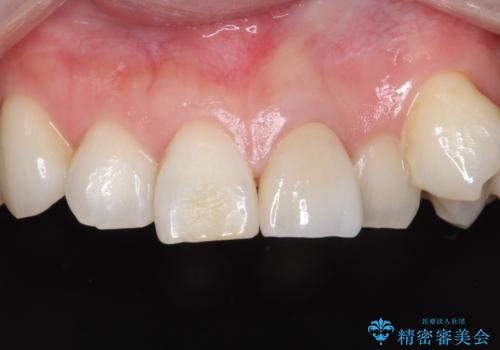

【根管治療】他院でインプラントの提案があった。奥歯が痛い。

- 左下の奥歯の治療の継続を主訴に来院されました。

1週間ほど前に、自発痛の既往があり他院で応急処置を行ってもらったとのことです。

そこでは、抜歯してインプラントの治療を提案されたとのことです。

レントゲンや口腔内所見にて以下のような説明ののち、患者様が保存を希望されたため、当院では根管治療~オールセラミッククラウンにて修復処置を行いました。痛みも消えて、経過良好です。